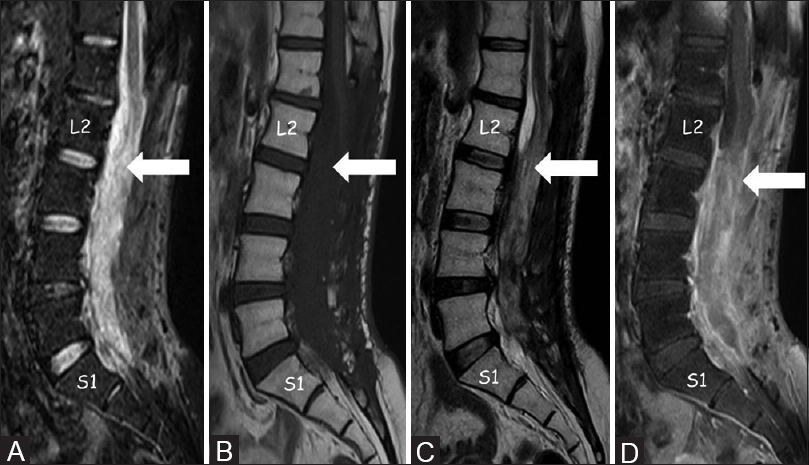

Magnetresonanz-Bildgebung (MRI)

Computerisierte Axialtomographie (CAT) -Scan